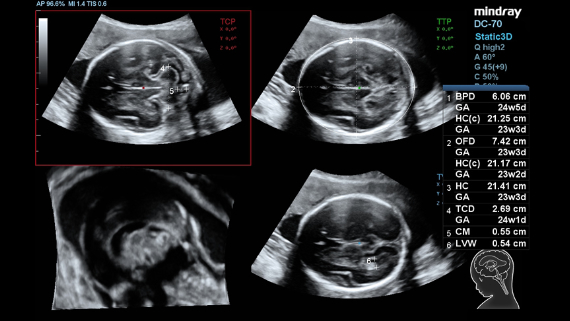

ImĂĄgenes clĂnicas